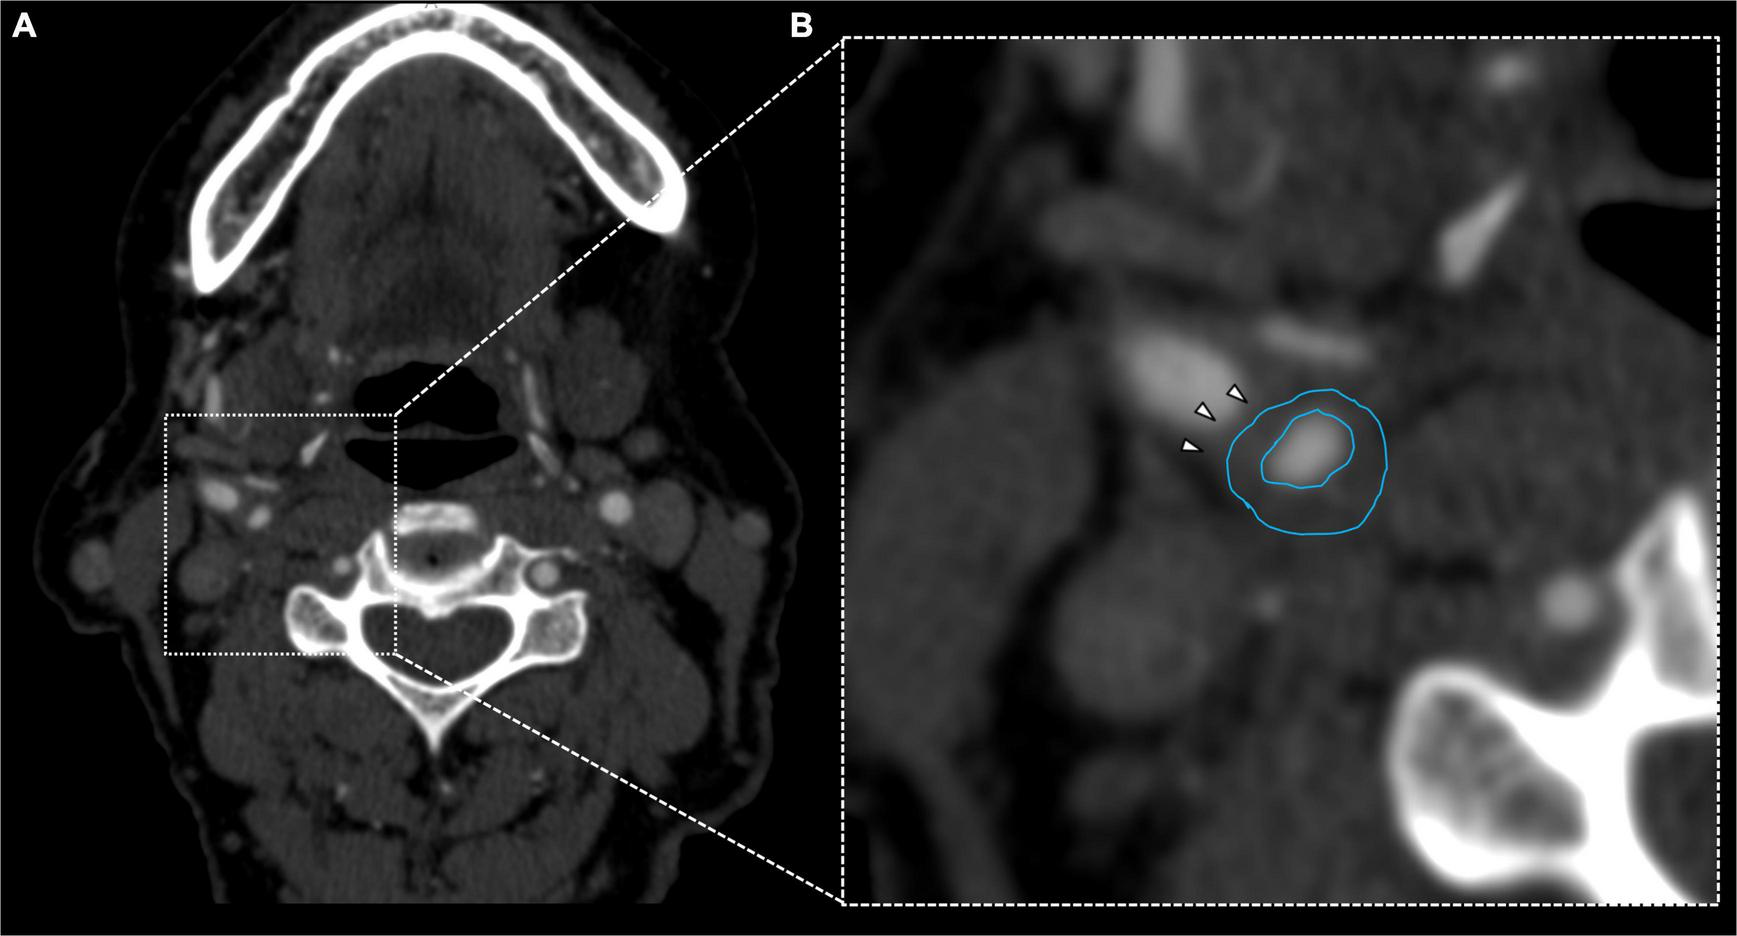

FIGURE 3

Fifty-six years old female showing fibrofatty plaque with concentric remodeling on right ICA (A). Plaque analysis confirmed the fatty composition of the plaque (B, white arrowheads).